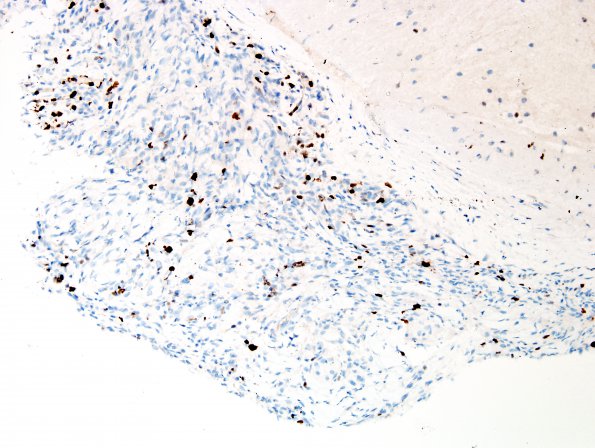

Washington University Experience | NEOPLASMS (PINEAL) | Papillary Tumor Pineal Region (PTPR) | 2E Papillary Tumor of the Pineal Region (Case 2) Ki67 1.jpg

Reactivity for proliferation marker Ki67 (MIB-1 antibody) stains tumor cell nuclei at variable density, ranging up to 4.0% ---- Ancillary data (not shown): Reactivity for glial fibrillary acidic protein (GFAP) is strong in associated non-neoplastic tissues, but is not detected in cells that appear intrinsic to the neoplasm. Reactivity for epithelial membrane antigen (EMA) stains only very rare putative paranuclear 'dots'. No reactivity for synaptophysin or neurofilament is noted within the neoplastic cells; the latter reveals only an exceedingly rare entrapped axon.